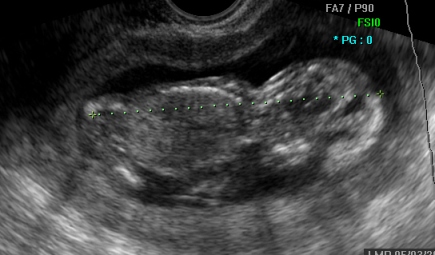

Покрај овие параметри, на овој преглед се испитува и мотилитетот (подвижноста) на бебето, се испитува растот, се земаат вообичаените мерки и се проверува дали големината на бебето соодветствува со неговата гестациска старост. Должината на бебето (CRL) изнесува околу 50 – 60 mm.

Во продолжение Ви презентираме неколку УЗ слики од прегледот во 12. недела.